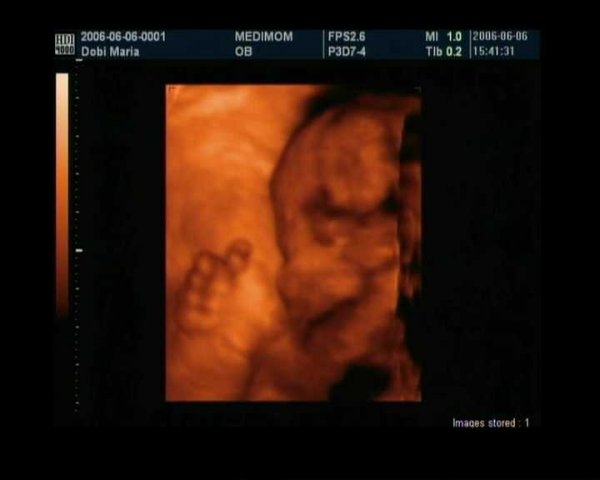

Olyan edi,hany hetes is itt???

Varom a penteket,megyek a Rozsakertbe ultrahangra,jon anyukam is.